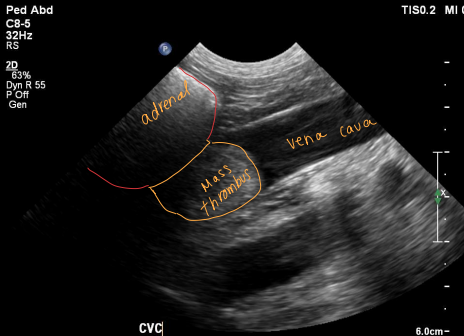

Pheochromocytoma

Medulla = ¼ of adrenal gland

Malignancy of chromaffin cells

local invasion

metastasis

Et: adrenal medulla tumor, excess catecholamines

Epinephrine, norepinephrine

Rare, 12y, dogs>cats

Cs: Restlessness / anxiety / pacing, intermittent collapse, hypertension, PU/PD, tachypnea, Epistaxis, blindness

Dt: CS & PE, imaging, urine normetanephrines

Tx: adrenalectomy (pre-op phenoxybenzamine →α-adrenergic antagonist)